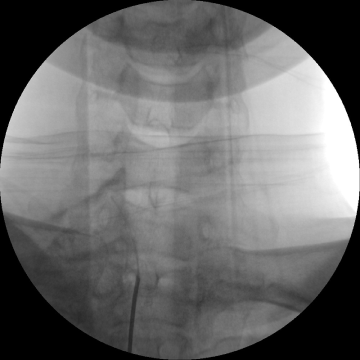

고주파수핵성형술

2017.08.07